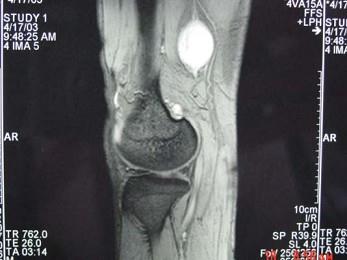

问题 男,48岁,腘窝上方疼痛2年余,呈持续性钝痛,且疼痛逐渐加重,曾以"结核”治疗无明显好转,体检腘窝上方肿胀,局部压痛,实验室检查均正常,请结合所提供的图像,选择最佳选项 ( )

选项 A、腘窝上方神经鞘瘤 B、腘窝上方脓肿 C、腘窝上方血管瘤 D、腘窝上方肌腱神经纤维瘤 E、腘窝上方囊肿

答案 D